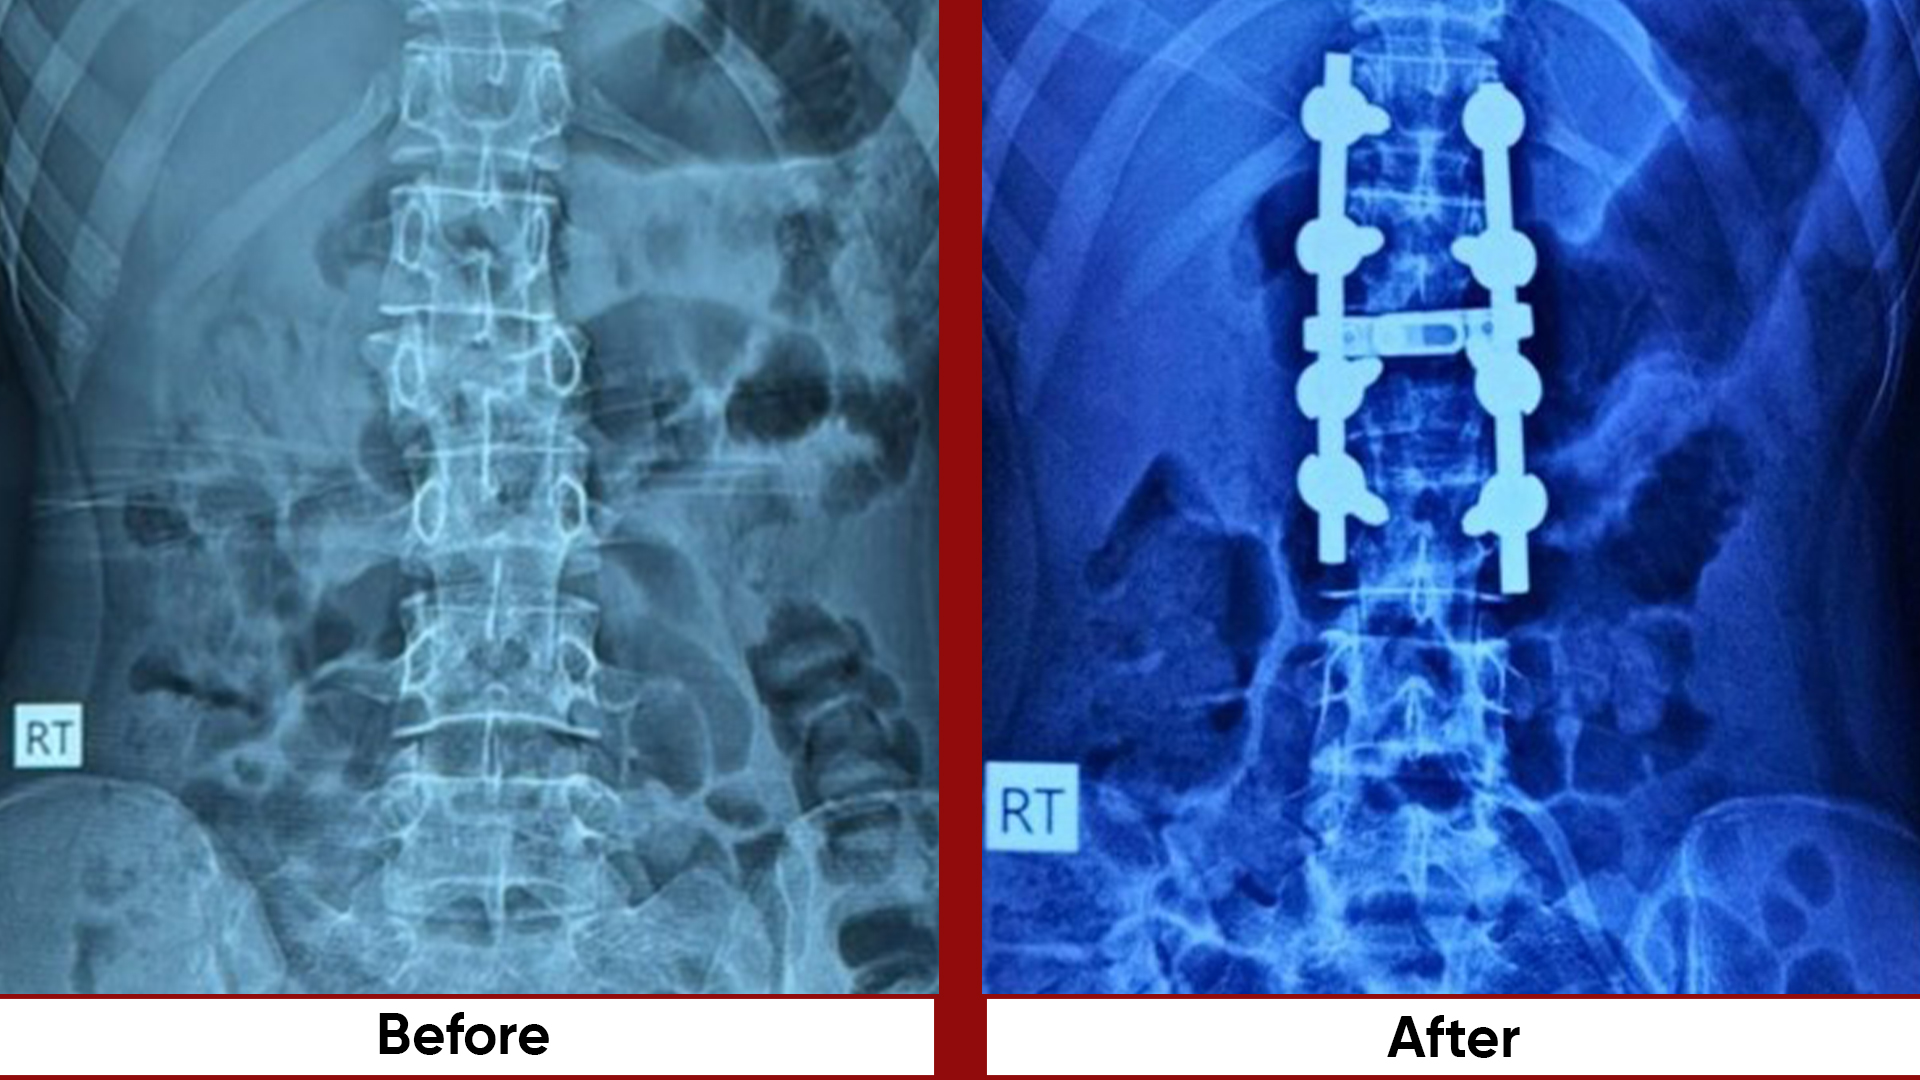

Procedures

• Total Knee Replacement (TKR)

• Total Hip Replacement (THR)

• Fracture Management (simple and complex trauma)

• Arthroscopic Surgeries (Knee & Shoulder)

• Joint Preservation Surgery

• Deformity Correction (limb lengthening, bowlegs, knock knees)

• Osteotomies (bone realignment surgeries)

• Bone Tumor Management

• Pelvic & Acetabular Fracture Fixation

• Hand and Microsurgery